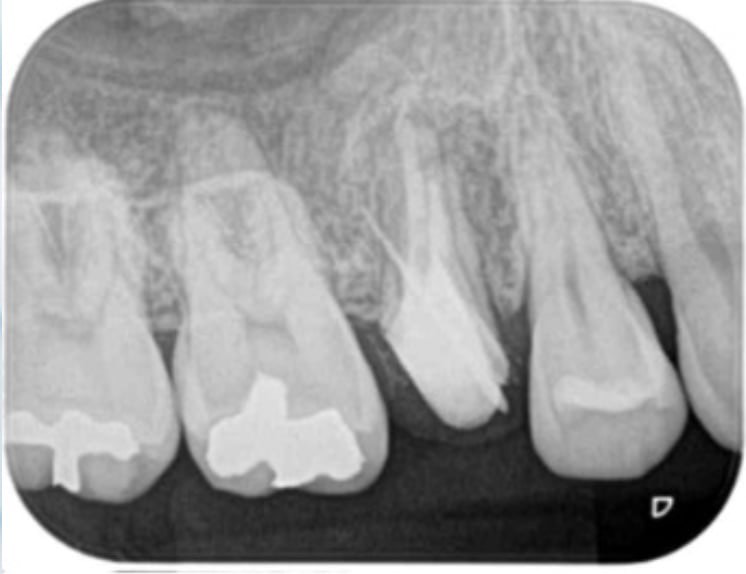

支台築造(根管治療が終了してから被せる前の土台)

すでに感染している。もしくは被せ直しをするために念のため内部を再度綺麗にする治療です。

当院で支台築造を行う場合は根管治療後可能な限り早くラバーダム下で無菌的処置環境を徹底して行います。 紹介元の歯科医院で支台築造を行なっても問題ありませんが、その際は連絡(報告書やEメールなど)し連携に配慮いたします。